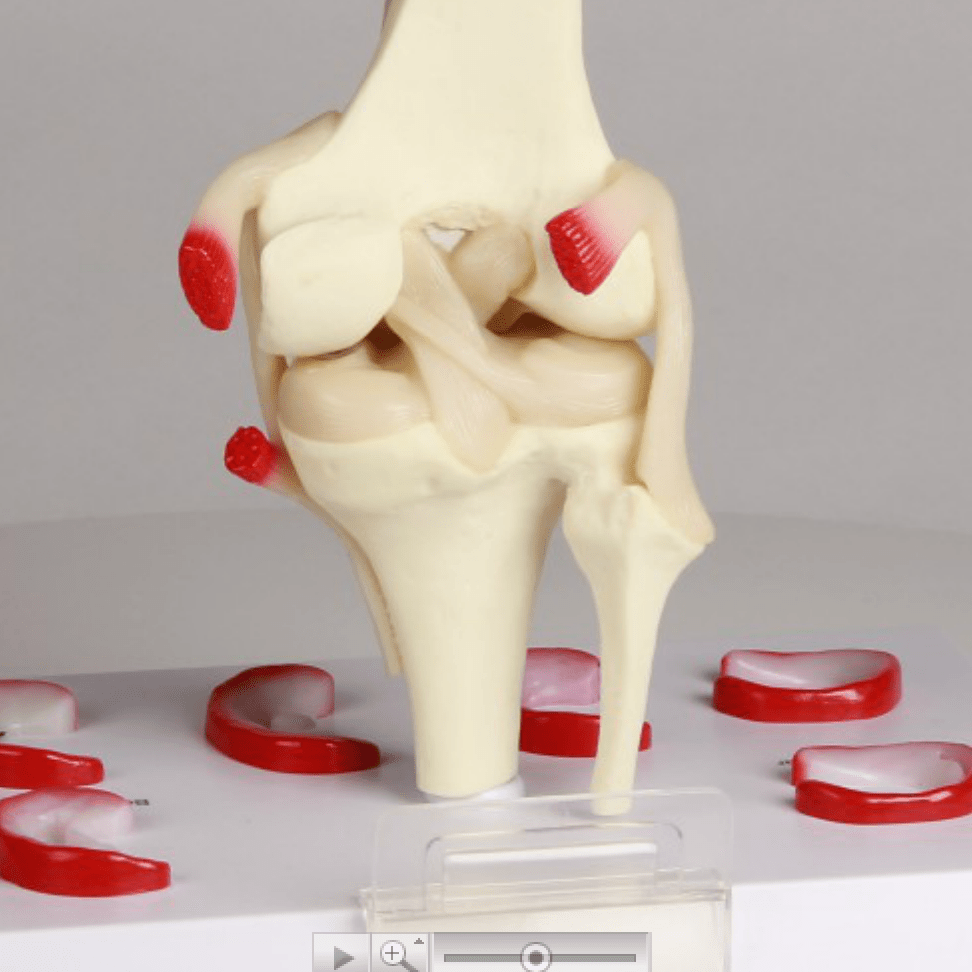

Salg af anatomiske modeller er det bærende element i eAnatomi, selvom vi også bruger mange ressourcer på at udvikle vores egne anatomiske materialer som fx plakater. Anatomiske modeller anvendes til forskellige formål og kan både vise afgrænset væv, organer samt organsystemer. Søger du en simpel model af knoglevæv eller måske en avanceret torso-model baseret på MRI teknologi, kan du finde det hele på eanatomi.com.